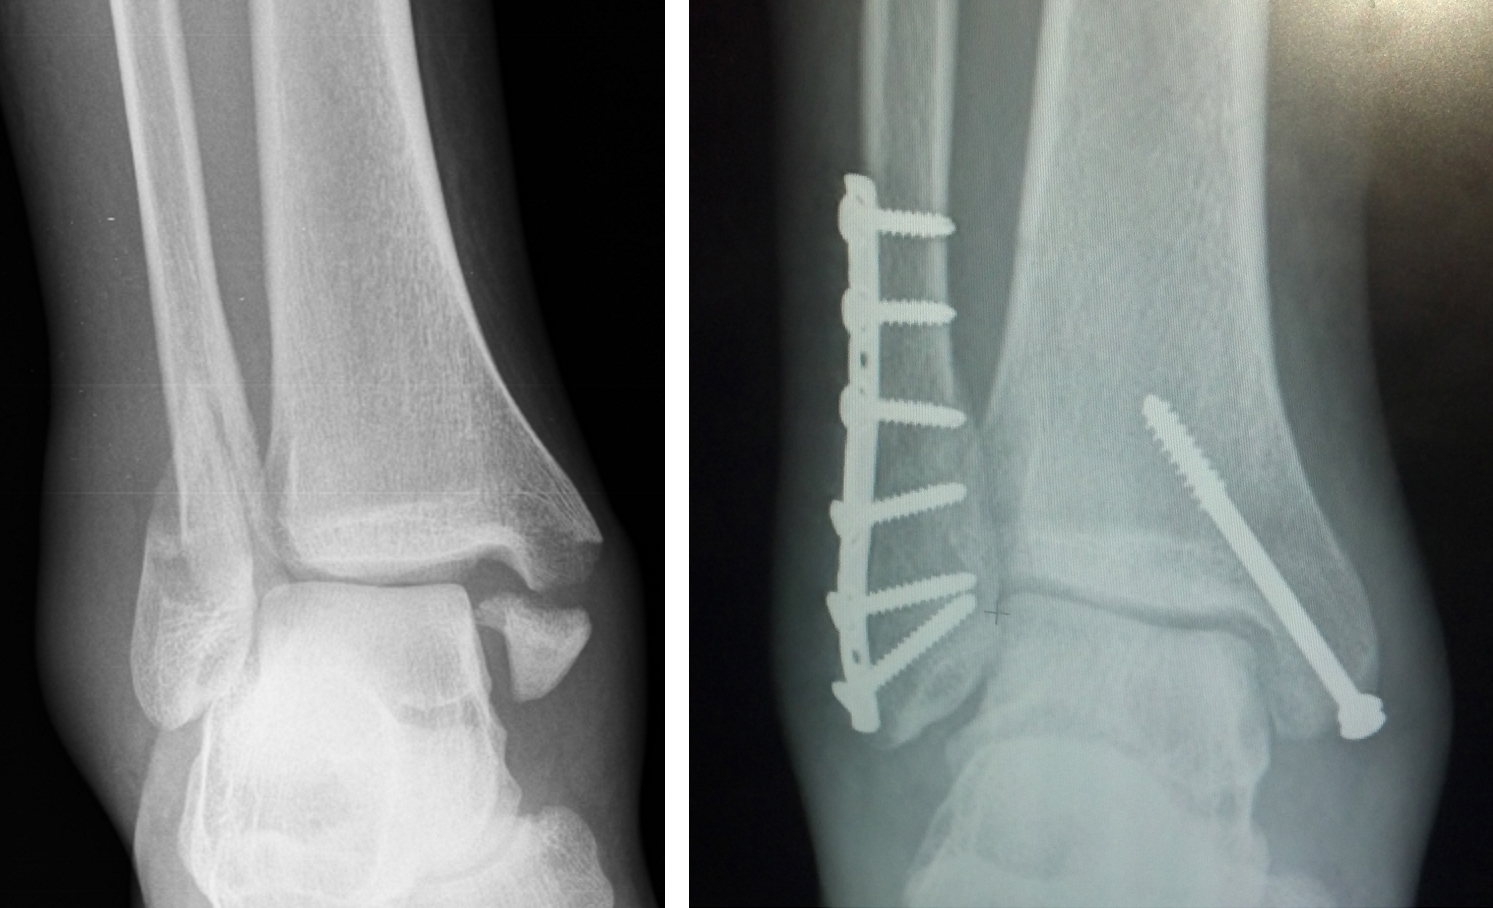

발목 염좌에서 X-ray는 아주 중요한 역할을 하는데요, 바로 골절을 감별해주기 때문입니다. 생각보다 일상생활에서 발생한 발목 염좌로 인해 병원에 오신 분들 중에서, 골절이 동반되는 경우가 많이 있습니다. 격한 운동을 하지 않았더라도, 본인의 체중이 발목에 온전히 실린채로 넘어지거나 미끄러지는 경우에, 하이힐을 신거나 게단을 내려오던 중에도, 골절이 발생하는 경우가 있습니다. 불완전 골절이나 골절 자체가 흔히 말하는 '금만 간 골절'인 경우, 다시말해 골절편의 전위 (어려운 말이죠)가 없는, 또 쉽게 말하자면, '뼈는 부러졌지만 부러진 뼈조각이 원래 자리에서 벗어나지 않은' 골절이라면 X-ray로 진단 후에 석고 부목으로 고정을 함으로써 비수술적 치료를 시도할 수 있습니다.

하지만 X-ray상에서 골절된 뼈가 원래 위치에서 벗어나있는 경우에는, 요즘은 대부분 빠른 일상생활로의 복귀와 추후 발생할 합병증을 최소화 하기 위해, 수술적 처치를 하게 됩니다.

2) X-ray상 골절이 확실하고, 수술을 계획하는 경우

골절 수술은 일종의 퍼즐맞추기와 같다고 할 수 있습니다. 제자리에서 떨어져나간 뼈조각을 원래 위치에 맞추어 고정을 시켜야 하는 수술입니다. 이를 위해서 수술전에는 내가 어떠한 기구를 이용하여 어느 방향으로부터 진입해서 뼈조각을 고정할 지에 대한 계획을 하게되는데요, 이를 CT 검사를 통해 도움을 받을 수 있습니다. X-ray로도 할 수 있지만은, 앞서 말씀드린 것처럼 그림자만으로 계획을 했을 경우에 만약에라도 발생할 불상사를 예방하기 위해서라도, 좋은 수술 결과를 바란다면 CT검사를 하는 것이 좋습니다.